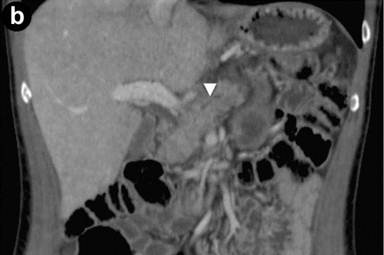

A 43-year-old man referred to us for abdominal pain and weight loss. IgG4 levels were elevated (298 mg/dL). Coronal scans with contrast enhanced CT (Image 3ab) showed the pancreatic head was enlarged with hypodense areas (2.7 cm, arrow) without vascular involvement of the mesenteric vessels. The pancreatic duct was dilated in both the body and the tail regions (arrowhead); the biliary tree was normal. The CT scan findings suggested pancreatic cancer. EUS and EUS-FNB were requested. Linear scanning (Image 3c) showed an enlarged pancreatic head with a focal hypoechoic mass (22 mm measured with calipers) with irregular margins (arrowheads). Upstream dilatation of the main pancreatic duct (8 mm, measured with calipers) in the body-tail regions was associated with the echopoor focal lesion (arrowheads); the lesion had close contact with the superior mesenteric vein (Image 3d). On EUS Doppler study (Image 3e), the echopoor lesion of the pancreatic head (arrowheads) appeared hypovascular; the superior mesenteric artery (arrow) and vein were patent.